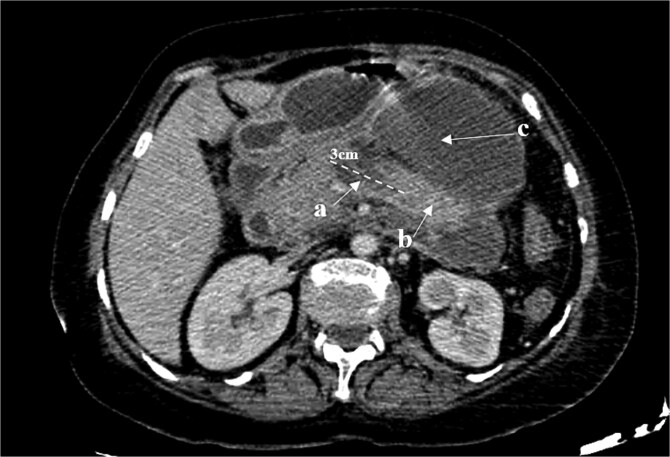

胰管断裂综合征(DPDS)是一种罕见的疾病,其特征是胰管断裂,使活的胰腺组织与胃肠道分离。它常伴随急性或慢性胰腺炎、腹部创伤或胰腺手术,导致导管坏死或解体。DPDS提出了重大的诊断和管理挑战,特别是在延迟发病的病例中。作者报告了一个坏死性胰腺炎后复发性胰液收集的复杂病例,强调了延迟DPDS表现的可能性。先进的成像技术,包括内窥镜超声检查,对比增强CT和MRCP,用于诊断。由于保守治疗失败,我们进行了远端胰腺切除术,解决了这个问题,并防止了感染、败血症或胰瘘等并发症。该病例强调了早期识别DPDS在影像学上的重要性,有助于及时治疗并降低长期并发症的风险。

Disconnected pancreatic duct syndrome (DPDS) is a rare condition characterized by a disruption of the pancreatic duct, separating viable pancreatic tissue from the gastrointestinal tract. It often follows acute or chronic pancreatitis, abdominal trauma, or pancreatic surgery, leading to ductal necrosis or disintegration. DPDS presents significant diagnostic and management challenges, especially in cases with delayed onset. The authors report a complex case of recurrent pancreatic fluid collections after necrotizing pancreatitis, highlighting the potential for delayed DPDS manifestation. Advanced imaging techniques, including endoscopic ultrasonography, contrast-enhanced CT, and MRCP, were used for diagnosis. Due to failure of conservative treatment, a distal pancreatectomy was performed, resolving the issue and preventing complications such as infection, sepsis, or pancreatic fistula. This case underscores the importance of early recognition of DPDS on imaging, facilitating timely treatment and reducing the risk of long-term complications.